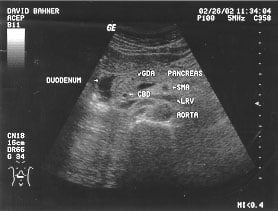

Aorta - suprarenal (labeled)